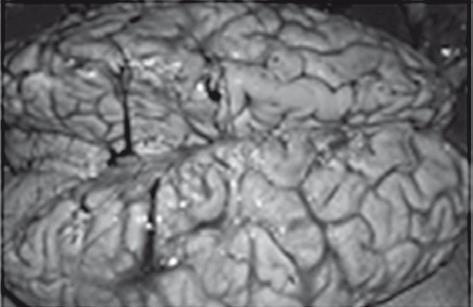

Иллюстрация к книге — Неалкогольная жировая болезнь печени [i_042.jpg]

Отек головного мозга